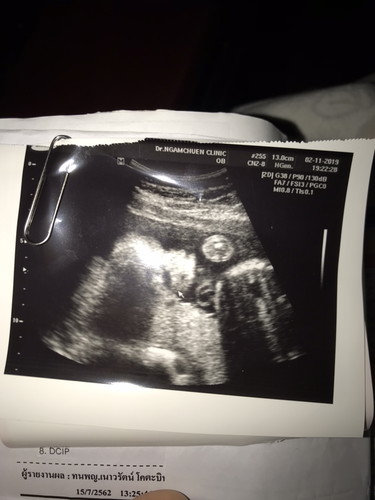

ในภาพน้องนอนหงาย จะเห็นส่วนหัวถึงหน้าอก

ส่วนหัวค่ะ หน้าน้องค่ะ

ภาพด้านข้างค่ะ

หูป่าวค่ะ